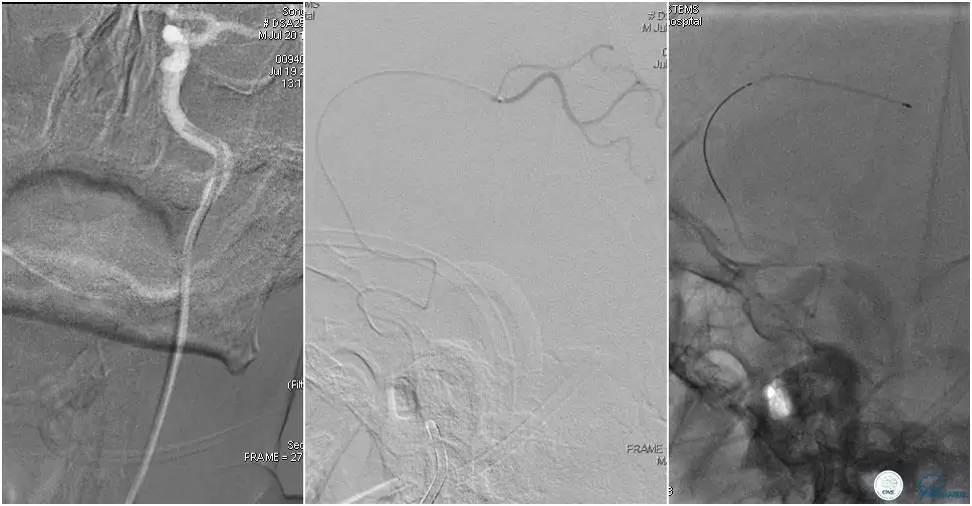

12:35穿刺告捷,TOT 185min。3型主动脉弓,右侧颈内动脉起始部狭窄70%,右侧大脑前动脉A1段未显影。

双侧大脑前动脉A4段闭塞,右侧大脑前动脉由左侧大脑前动脉经前交通动脉代偿供血。

6F Envoy置于颈内动脉C3段,选用Solitaire-FR 4*20mm支架释放于右侧大脑前动脉,完全覆盖血栓。

6F Envoy置于左侧颈内动脉C3段,选用Solitaire-FR 4*20mm支架释放于右侧大脑前动脉取栓1次,血流达TICI 2b。

Solitaire-FR 4*20mm支架释放于左侧大脑前动脉取栓1次,取出少许血栓重复造影左侧大脑前动脉胼周动脉开口后,右侧大脑前动脉A2段以远未显影,斟酌栓子逃逸。

选用Solitaire-FR 4*20mm支架分别于右侧大脑前动脉A2-A3段,左侧胼周动脉,右侧胼周动脉取栓3次。

双侧大脑前动脉完全显影,TICI 3级,TOR 261min。